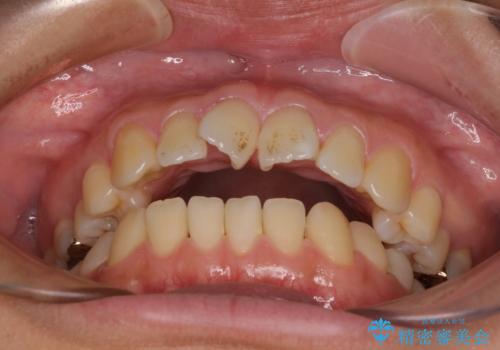

- ぼろぼろになった奥歯を治療したいとのことで来院された患者様です。

重度の歯周病と歯列不正が認められたため、歯周病治療やインプラントによる咬合回復を行った後に矯正治療を実施し、最終的にオールセラミッククラウンに補綴することとしました。

インプラント治療や歯槽骨再生治療、矯正治療など、盛りだくさんの治療計画であったため、治療期間は最低でも4年という予想でした。

歯列不正などによるプラークコントロールの不良が治療を困難なものとしましたが、矯正治療後は歯肉の状態も落ち着き、安定した状態でオールセラミッククラウンの補綴を行うことができました。